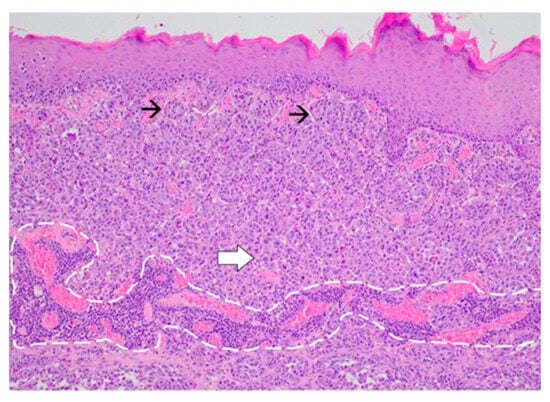

2. Case Presentation